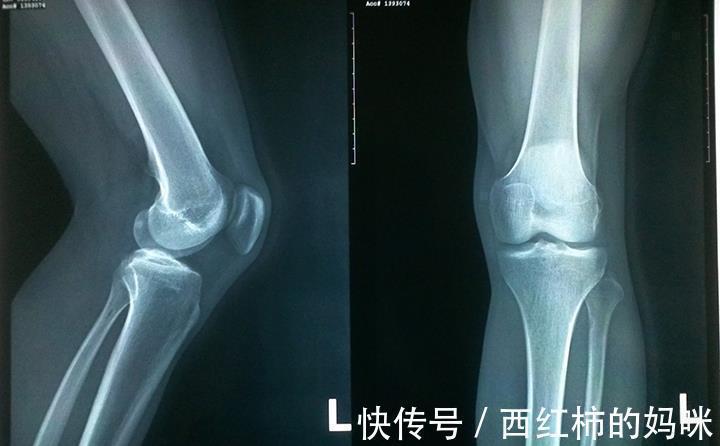

由于饮食与生活环境,早熟已经是很常见的现象,早熟让骨骼年龄超前生长,超过实际年龄,长高幅度因此大大下降。